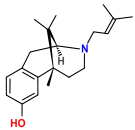

Benzomorphans

- 5,9 alpha-diethyl-2-hydroxybenzomorphan (5,9-DEHB)

- 8-Carboxamidocyclazocine (8-CAC)

- Alazocine

- Anazocine

- Bremazocine

- Butinazocine

- Carbazocine

- Cogazocine

- Cyclazocine

- Dezocine

- Eptazocine

- Etazocine

- Ethylketazocine

- Fedotozine

- Fluorophen

- Gemazocine

- Ibazocine

- Ketazocine

- Metazocine

- Moxazocine

- Pentazocine

- Phenazocine

- Quadazocine

- SKF-10047

Structures

| Benzomorphans | ||||

|---|---|---|---|---|

5,9 alpha-diethyl-2-hydroxybenzomorphan 5,9 alpha-diethyl-2-hydroxybenzomorphan (5,9-DEHB) |

8-Carboxamidocyclazocine 8-Carboxamidocyclazocine |

Alazocine Alazocine |

Anazocine Anazocine |

Bremazocine Bremazocine |

Butinazocine Butinazocine |

Carbazocine Carbazocine |

Cogazocine Cogazocine |

Cyclazocine Cyclazocine |

Dezocine Dezocine |

Eptazocine Eptazocine |

Etazocine Etazocine |

Ethylketocyclazocine Ethylketocyclazocine |

Fedotozine Fedotozine |

Fluorophen Fluorophen |

Gemazocine Gemazocine |

Ibazocine Ibazocine |

Ketazocine Ketazocine |

Metazocine Metazocine |

Moxazocine Moxazocine |

Pentazocine Pentazocine |

Phenazocine Phenazocine |

Quadazocine Quadazocine

|

Thiazocine Thiazocine |

Tonazocine Tonazocine |

Volazocine Volazocine |

Zenazocine Zenazocine |